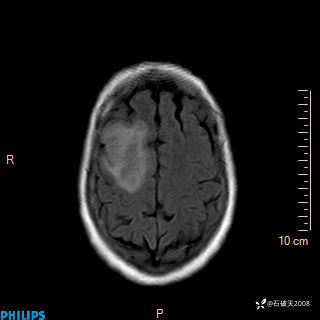

2020.11.14MR

FLAIR